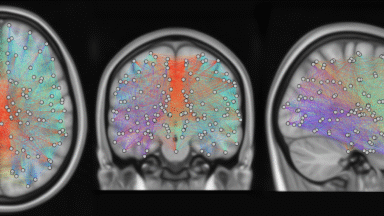

Graph Phase based Clustering on Rest and Task fMRI

For many years, wide variety of clustering methods have been employed in neuroimaging, revealing crucial network-wide patterns. Instances of such work include, functional networks (e.g Default Mode Network) …

Graph signal processing to investigate structure-function coupling during sleep

Brain functional activity emerges from the underlying anatomical structure of neural fiber bundles in a non trivial way. Considering functional magnetic resonance imaging (fMRI) recorded signals as defined on the structural graph allows us to address this question in the graph signal processing framework, adapting conventional signal processing concept to the …